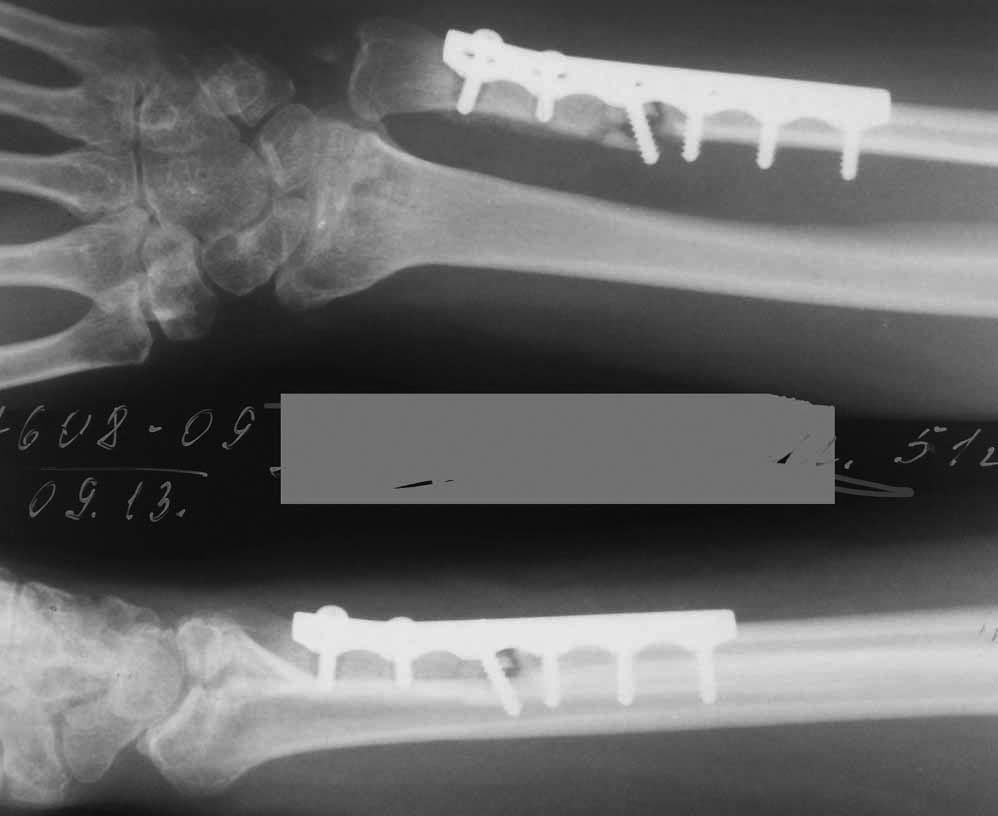

Обратилась пациентка, которой по поводу неправильно сросшегося перелома дистального эпиметафиза лучевой кости была выполнена корригирующая остеотомия локтевой кости. В феврале этого года пациентке, с ее слов и по данным выписки, была выполнена укорачивающая остеотомия локтевой кости по типу "русского замка". Основанием такого решения послужили жалобы больной на лучевую косорукость вследствие неправильно нелеченного перелома дистального эпиметафиза лучевой кости (давность около 3 месяцев). В настоящий момент беспокоят жалобы на сильные боли в области лучезапястного сустава, "щелчки" при движениях кистью и вращении предплечья. Пользоваться левой кистью по назначению не может. Послеоперационный рубец нормотрофический. Рана зажила первичным натяжением.

Rg-здоровой руки

Возможно причина в несращении локтевой кости. На рентгенограмах прослеживается резорбция кости вокруг винтов на дистальном отломке, отсутствует сращение.

По простым снимкам (а по КТ еще лучше) видно, что суставная поверхность отклонена к тылу, кисть на подвывихе, есть внутрисуставная деформация. Укорочение локтевой кости только усилило проблемы, а тут еще и несращение...

Word, 149 Kb

Случай сложный и наверняка здесь действует несколько механизмов формирования боли. Это и ложный сустав локтевой кости, и тыльный подвывих кисти (хорошо виден на срезе КТ, обозначенном стрелкой), и нарушения в лучелоктевом сочленении, в т.ч., за счет не полностью и со смещением сросшегося дорсального фрагмента лучевой кости, и сужение карпального канала за счет смещения кисти к тылу. Поэтому, вмешательство на лучевой кости должно предполагать не только ее укорочение, но и коррекцию наклона суставной поверхности за счет разворота ладонного фрагмента (клиновидная остеотомия) и сопоставление его с тыльным фрагментом, для чего, вероятнее всего, понадобится разрушение имеющегося в области метадиафиза сращения тыльного и ладонного фрагментов. Во вложенном файле случай хотя и не идентичный, но похожий (5 лет после травмы). Боли и проявления синдрома карпального канала прошли только через 10-12 месяцев после операции.

Пациентка хочет, чтобы рука не болела. Наибольшая болезненность локализуется в проекции как раз дистального лучелоктевого сочленения. Так что это не устраивает не только меня но и пациентку. Избыточное укорочение локтевой кости привело к проксимальному вывиху ее головки.

Судя по Rg-грамме "биология" в зоне несращения отсутствует напрочь, что и понятно, учитывая насколько пришлось ободрать кость для формирования

"русского замка". Отсюда и желание мининвазивности, чтобы не убить окончательно.